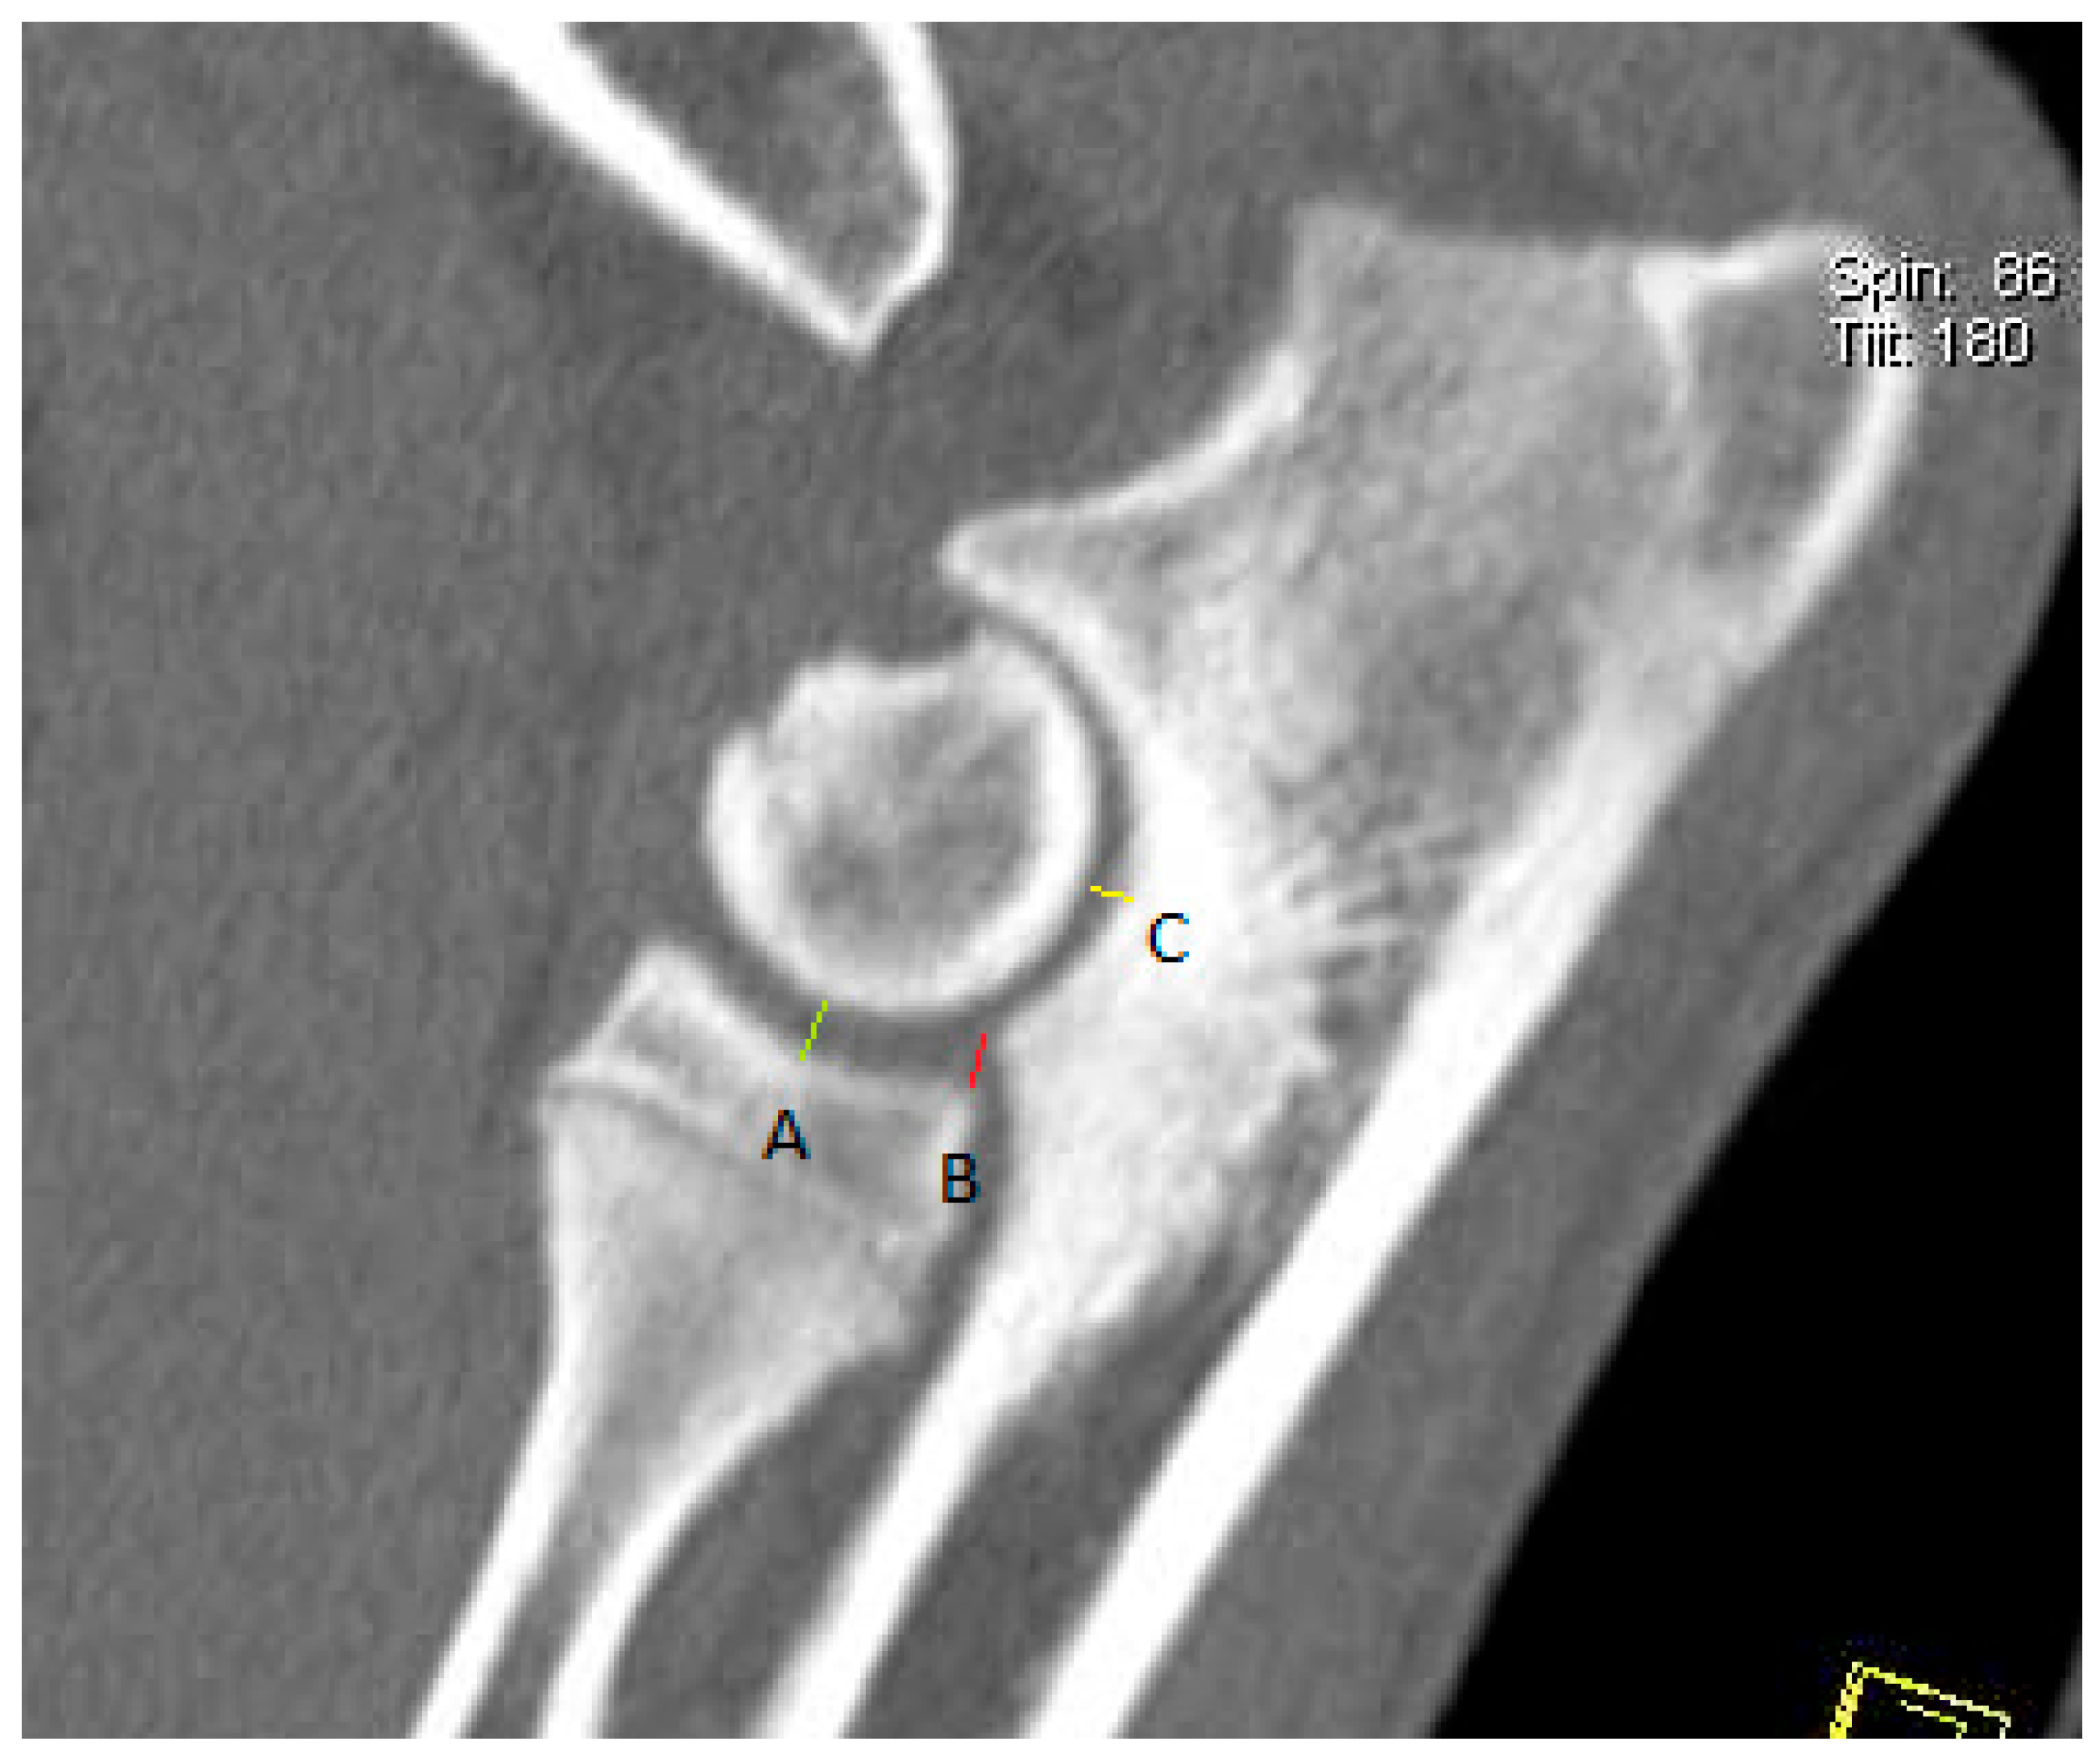

2.4. CT Technique

2.5. Measurement Techniques